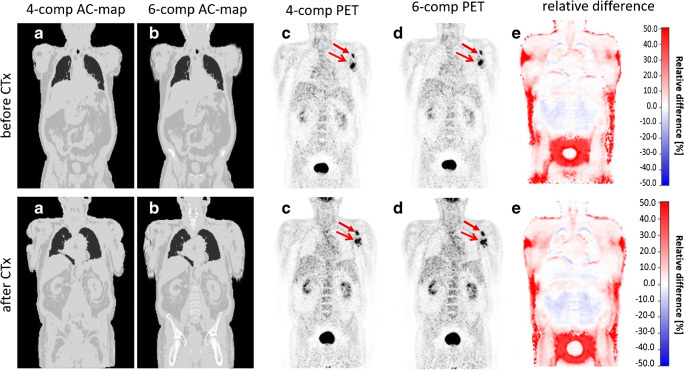

Patient case with injected 18F-FDG before and after chemotherapy (CTx): standard 4-compartment μ-map serving as reference (a) and improved 6-compartment μ-map (b) with corresponding corrected PET data to 4-compartments (c) and 6-compartments (d) with two marked lesions (red arrows) as well as calculated relative difference maps (e). The difference maps (e) again depict the quantitative differences between PET data reconstructed with the 4- and 6-compartment μ-maps. Note that all image panels (μ-maps, PET data, difference maps) show a high degree of comparability between both examinations before and after CTx, separated by 21 days, indicating high reproducibility. Quantitative results are provided in Table 3

One patient example is exhibited in Fig. 5 for a patient who had two PET/MR examinations before and after chemotherapy, separated by 21 days. Table 3 provides the measured SUVmax values of two bone lesions in this patient example for the 4-compartment μ-map and the 6-compartment μ-map with corresponding corrected PET data. Note that the relative impact of improved AC is highly comparable for each of the two lesions before and after chemotherapy. SUVmax of lesion no. 1 before chemotherapy increases by 5.4% due to 6-compartment AC while it increases by 5.2% after chemotherapy when comparing 6-compartment AC with 4-compartment AC as reference. Similar comparability can be seen for lesion no. 2, where the SUVmax increases by 8.9% before, and 10.0% following chemotherapy. In this patient example, the SUVmax of lesion no. 1 due to the impact of therapy decreased from 13.6 to 8.0 by 41.2%. The SUVmax of lesion no. 2 decreased from 14.7 to 9.9 by 32.6% between the two examinations.

Accuracy and repeatability of MR-based attenuation correction are important methodological preconditions to quantify the effect of therapy on specific tumors and lesions in a clinical setting. In this context, the results of Table 3 demonstrate accurate quantification of the effect of therapy on lesion activity. The results indicate a high repeatability of SUVmax quantification for each of the two lesions in two different examinations, separated by 21 days. Although applying the improved AC methods in this specific patient case did not have a direct clinical impact on patient or therapeutic management, applying the most accurate AC methods available is an important methodological precondition, as whole-body PET/MR hybrid imaging today is increasingly used as diagnostic hybrid imaging modality for monitoring of therapeutic responses [34,35].